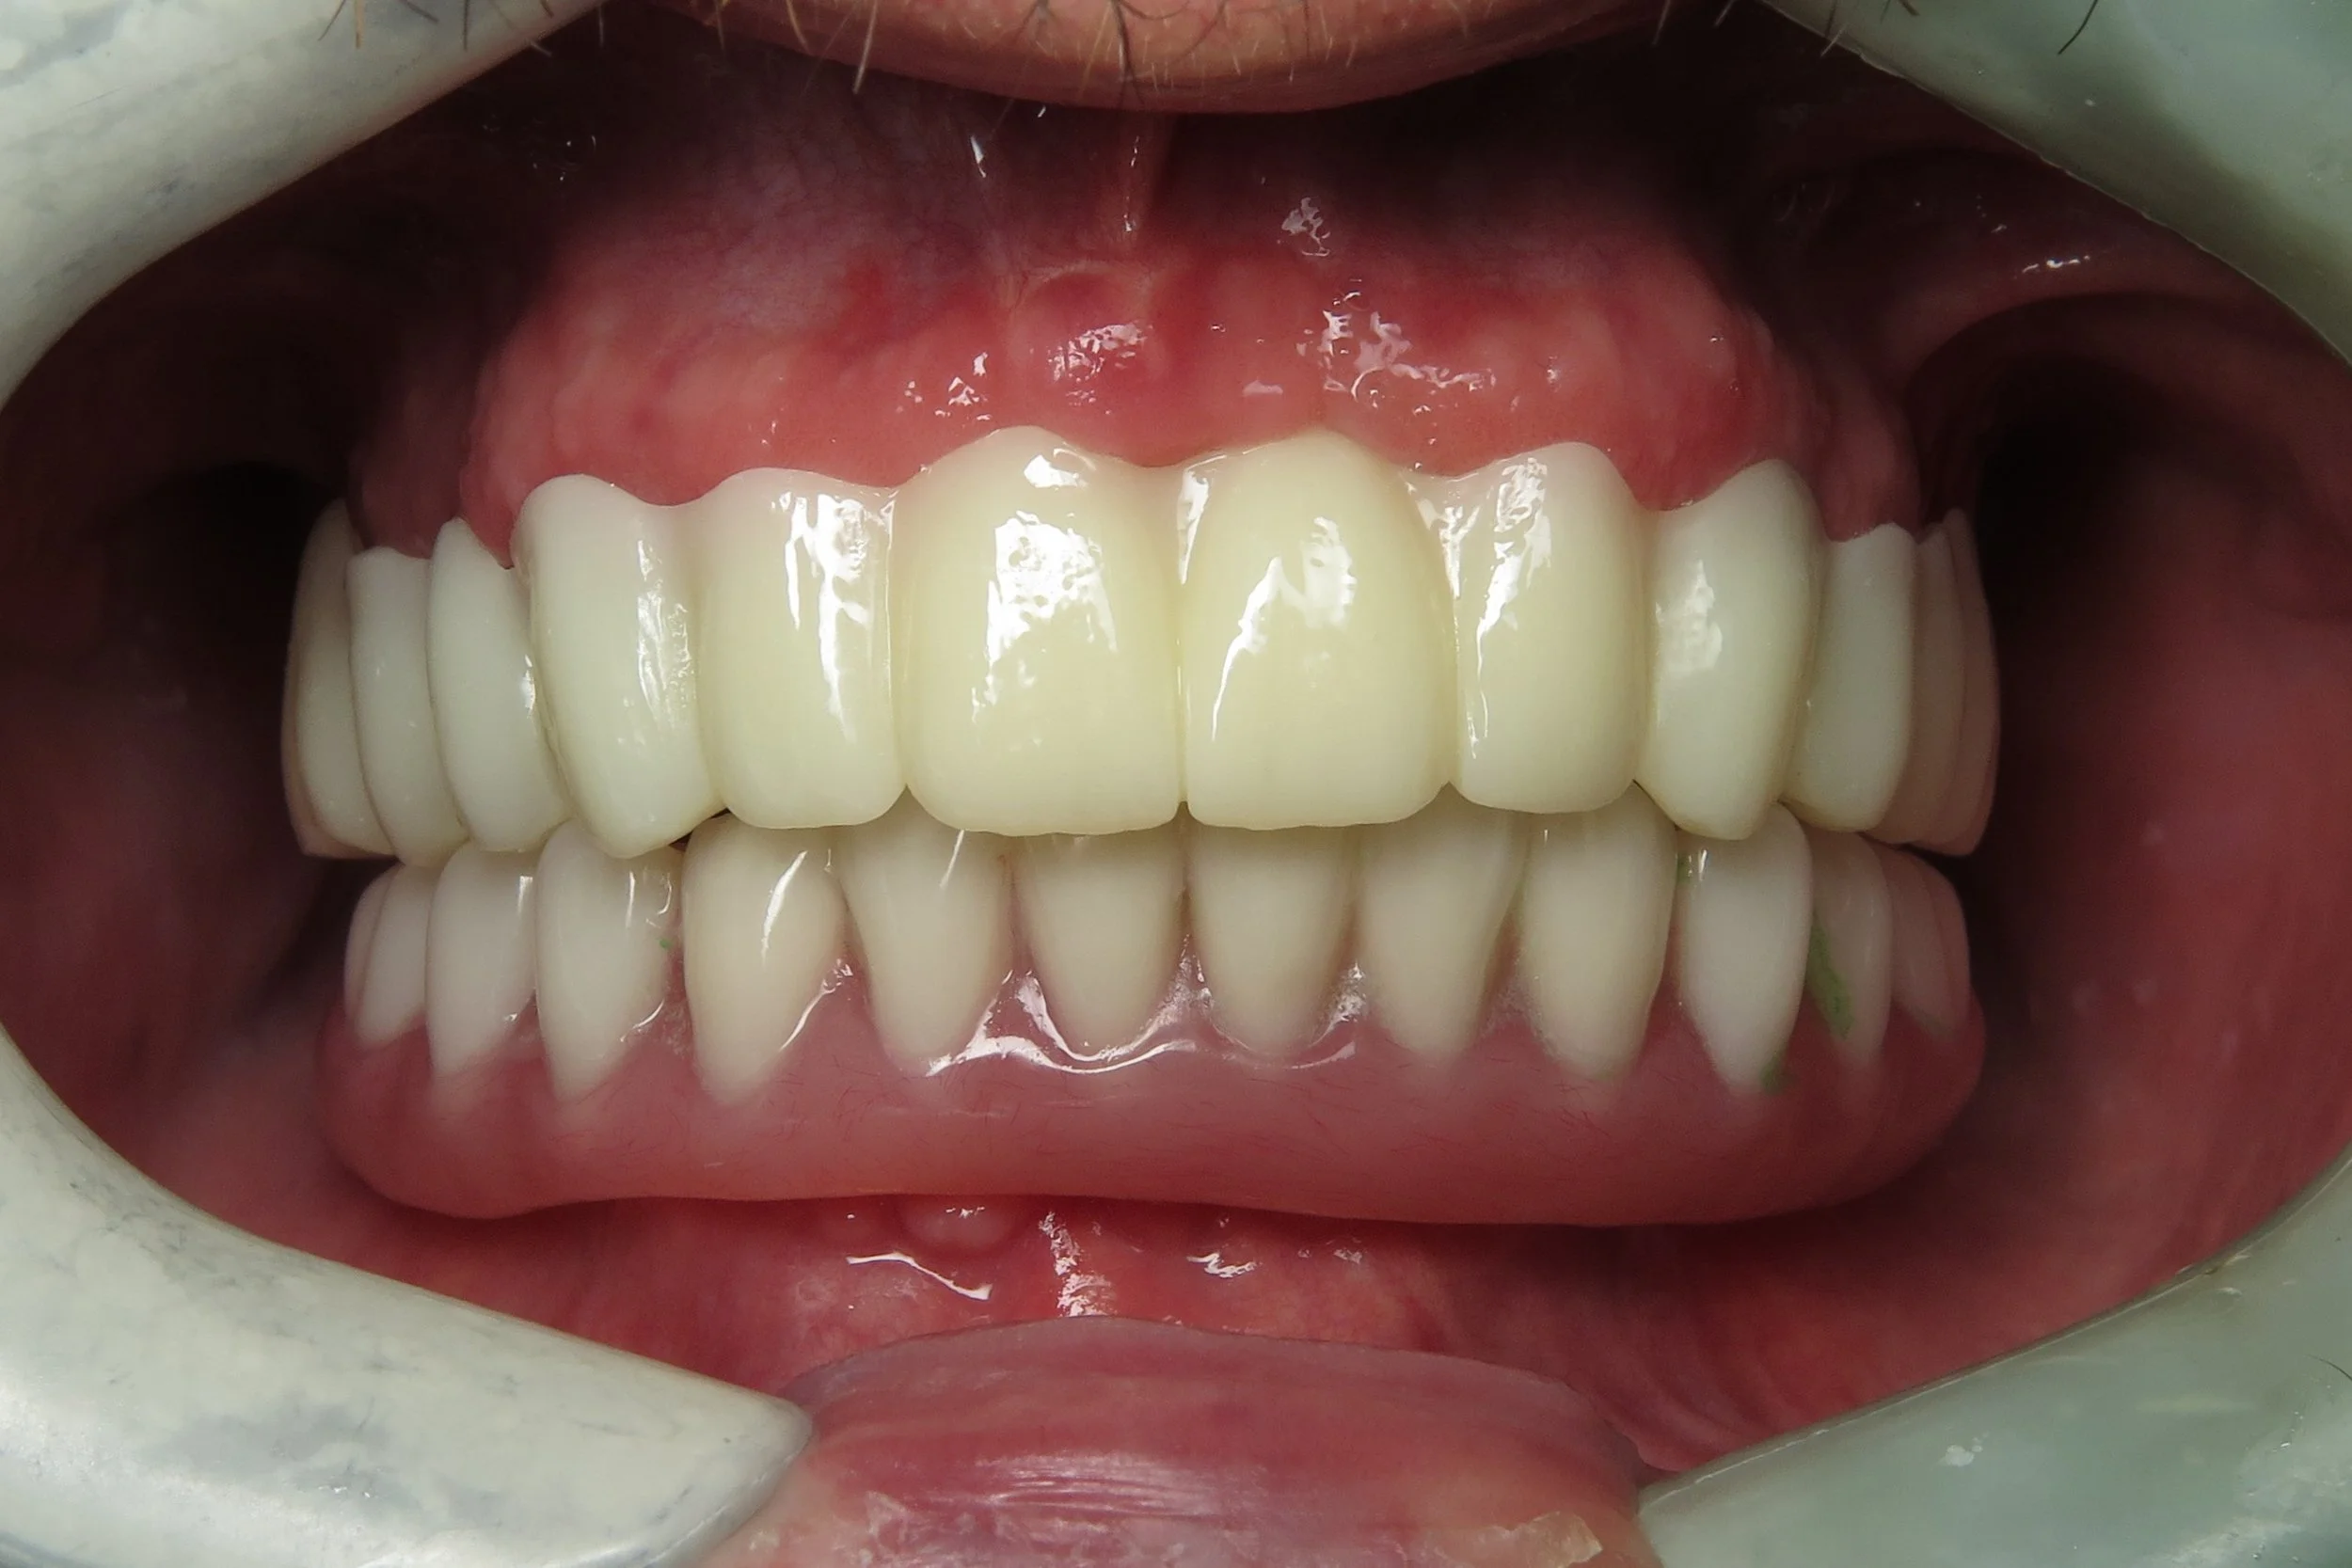

• Feels more like natural teeth due to the size and shape compared to a denture or an All on 4 fixed hybrid prosthesis.

The following cases were done by Dr. Johansen: